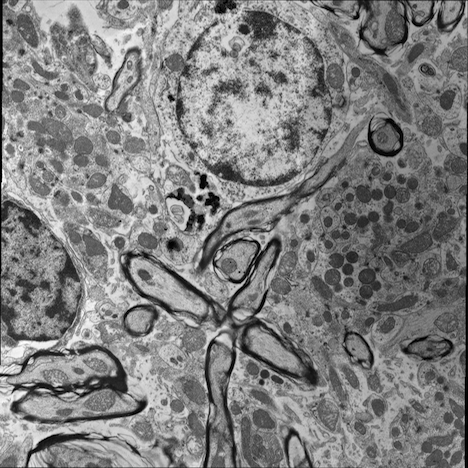

Correlative microscopy is an integration of different microscopy technologies including conventional light, confocal and electron transmission microscopy [6]. Correlative microscopic images usually involve linear or non-linear distortions which are caused by the differences between imaging systems and processing steps. Therefore, the first step of most correlative microscopy based applications is to do registration between two or more microscopic images. An example of correlative microscopic images is presented in Fig. 1.

Refer to caption

(a) Confocal Microscopic Image

(b) Resampling of Boxed Region in Confocal Image

(c) TEM Image

Figure 1: Example of Correlative Microscopy. The goal is to align (b) to (c).